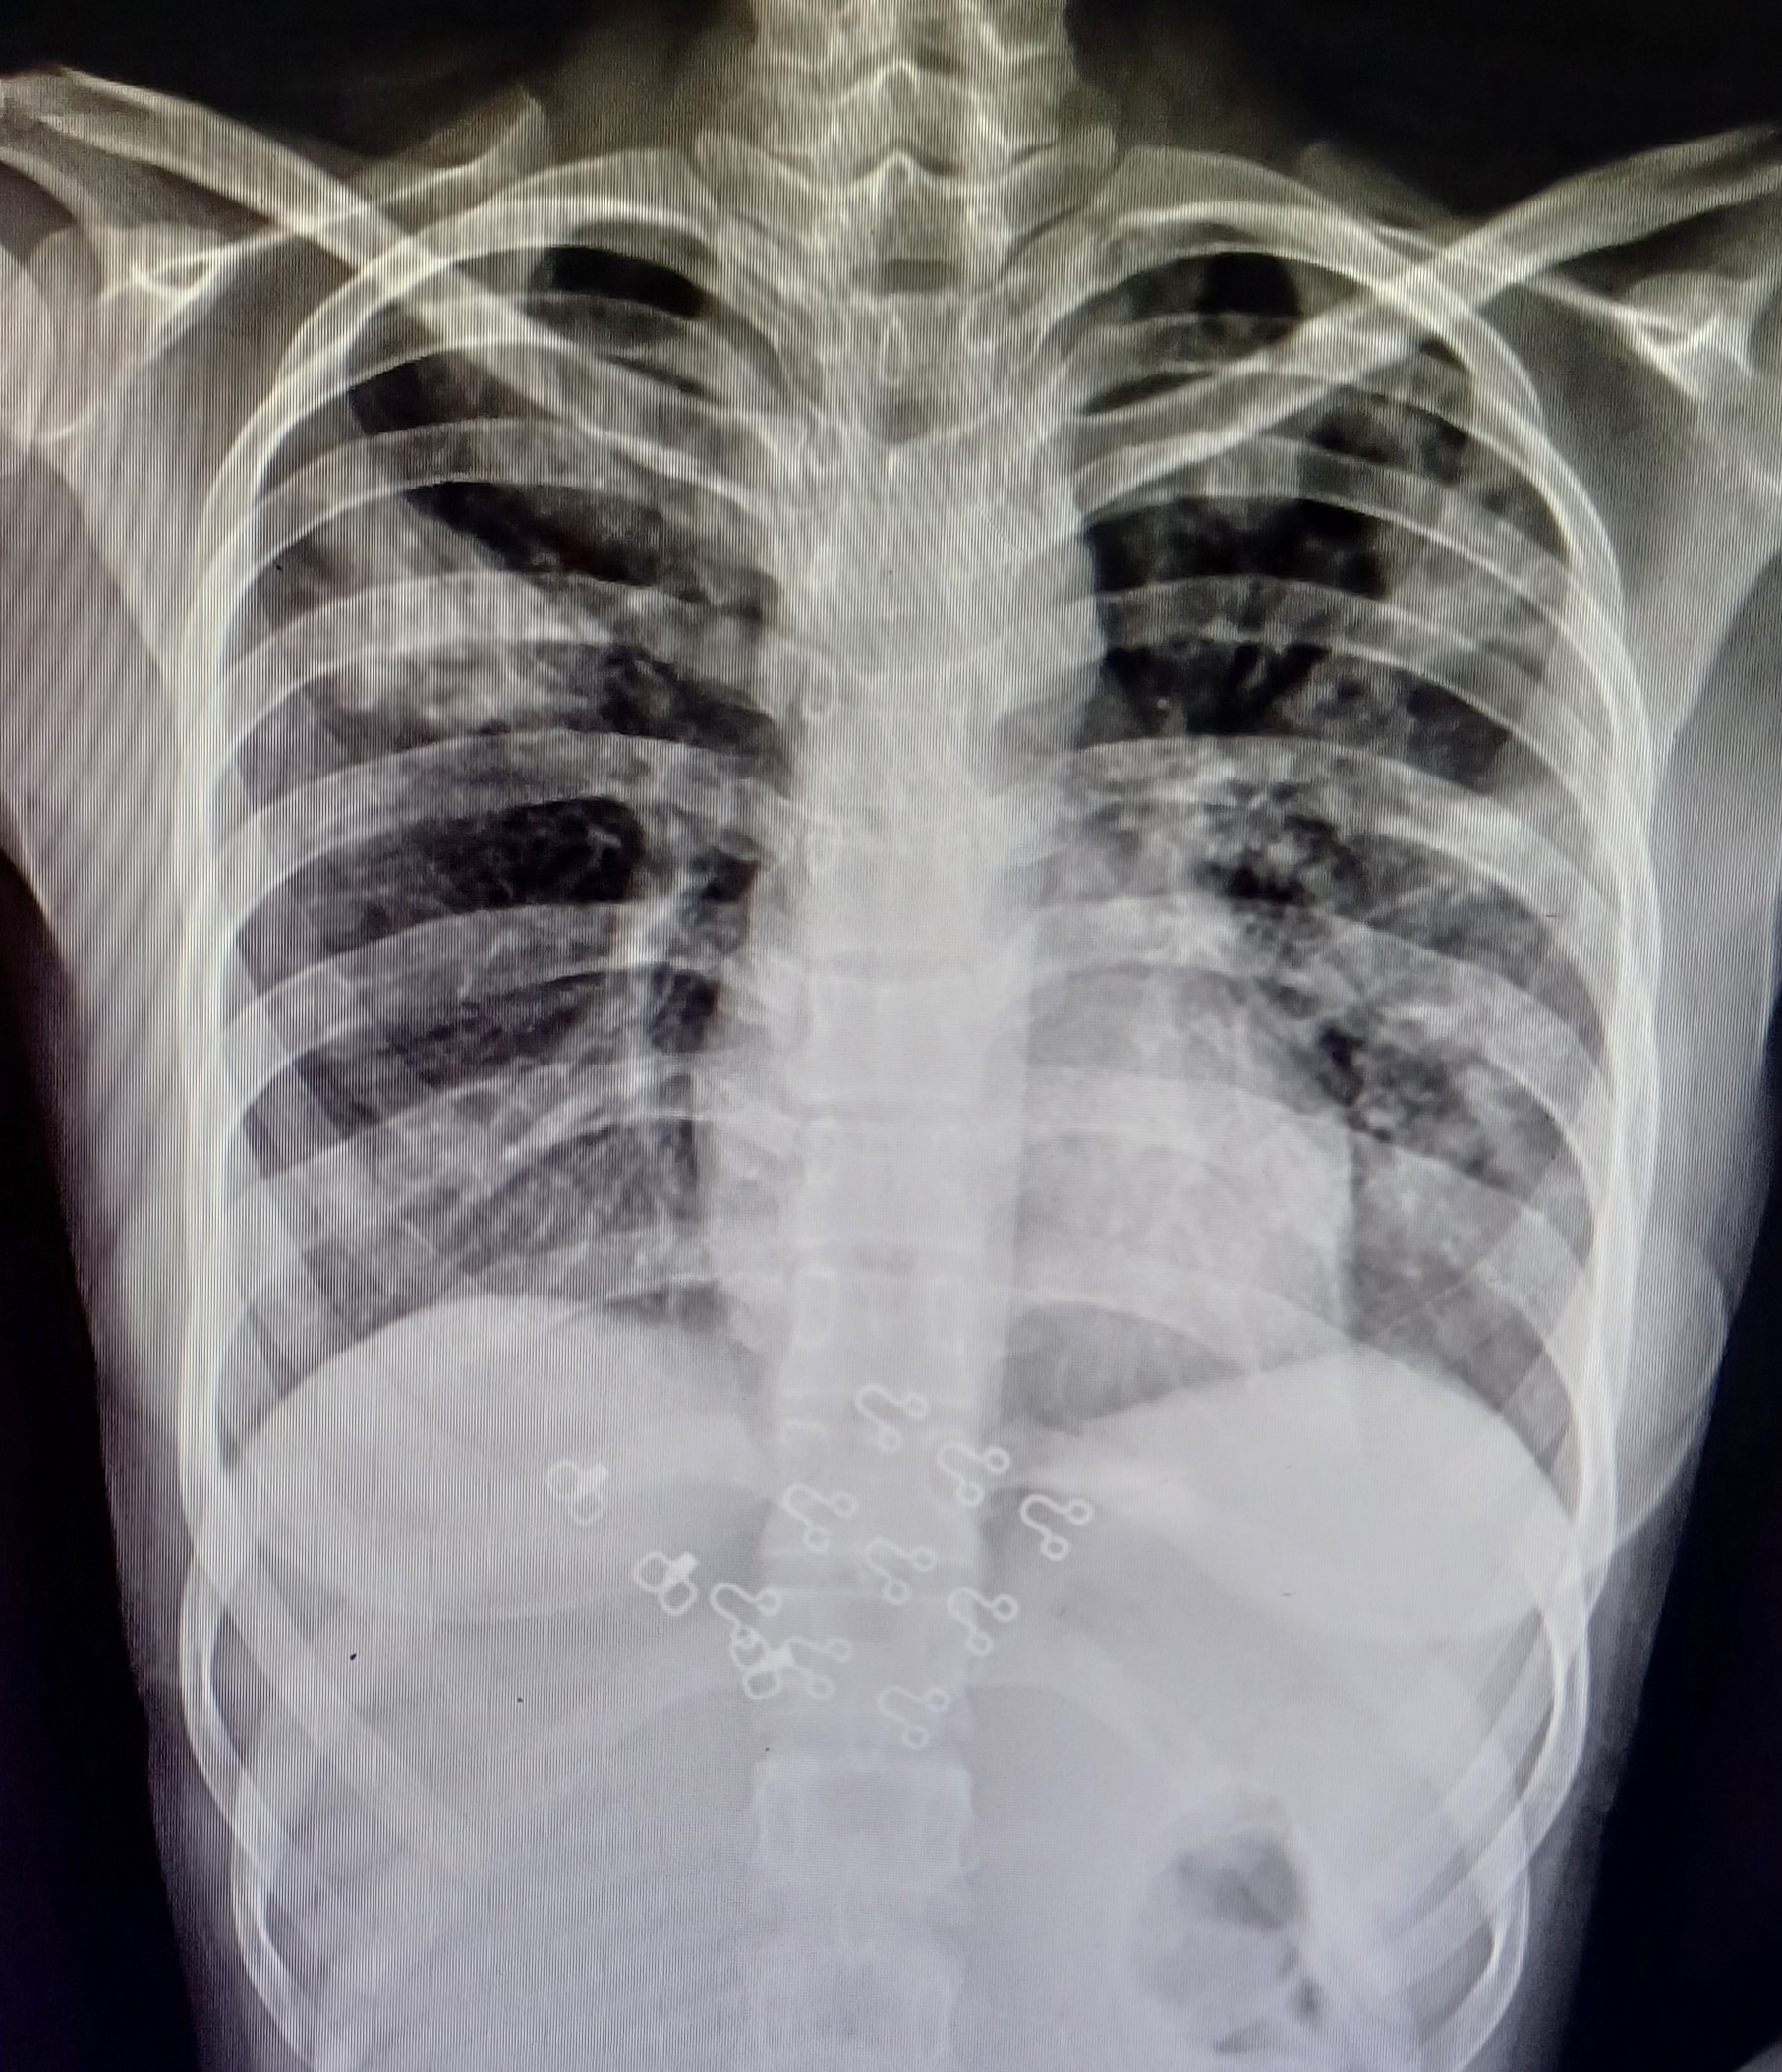

| 7 | IGGMC, Nagpur, Nagpur | P2 | 29-4465 | Ibrahim Pathan | Consent taken on Paper | 21 Yrs. |

Provisional Diag : Pleural Effusion ?

Final Diag : Tubercular Pleural effusion (Clinically Diagnosed Tubercular Pleural effusion) |

TB Case (Confirmed) | Right sided pleural effusion | Abnormality visible on x-ray |